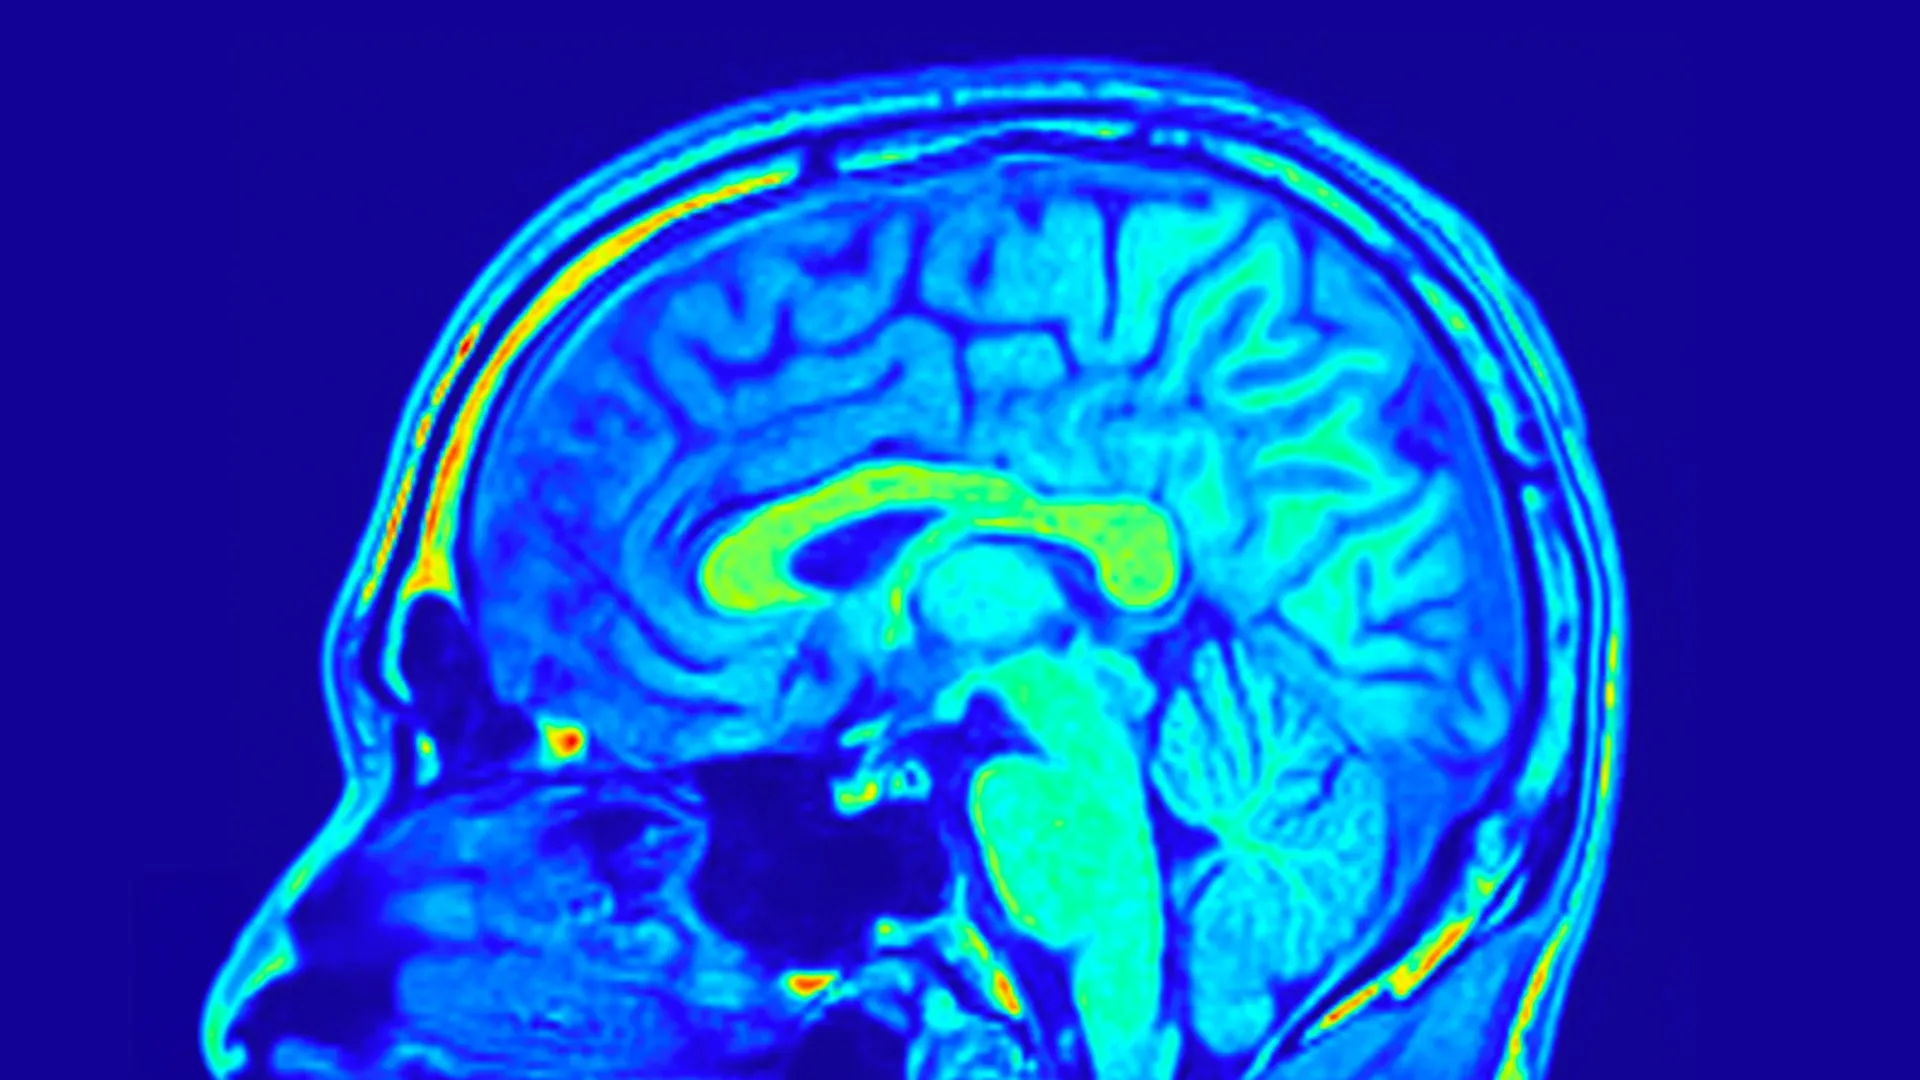

Brain scans may finally end the guesswork in depression treatment

Major depressive disorder (MDD) is a widespread and serious mental health condition…